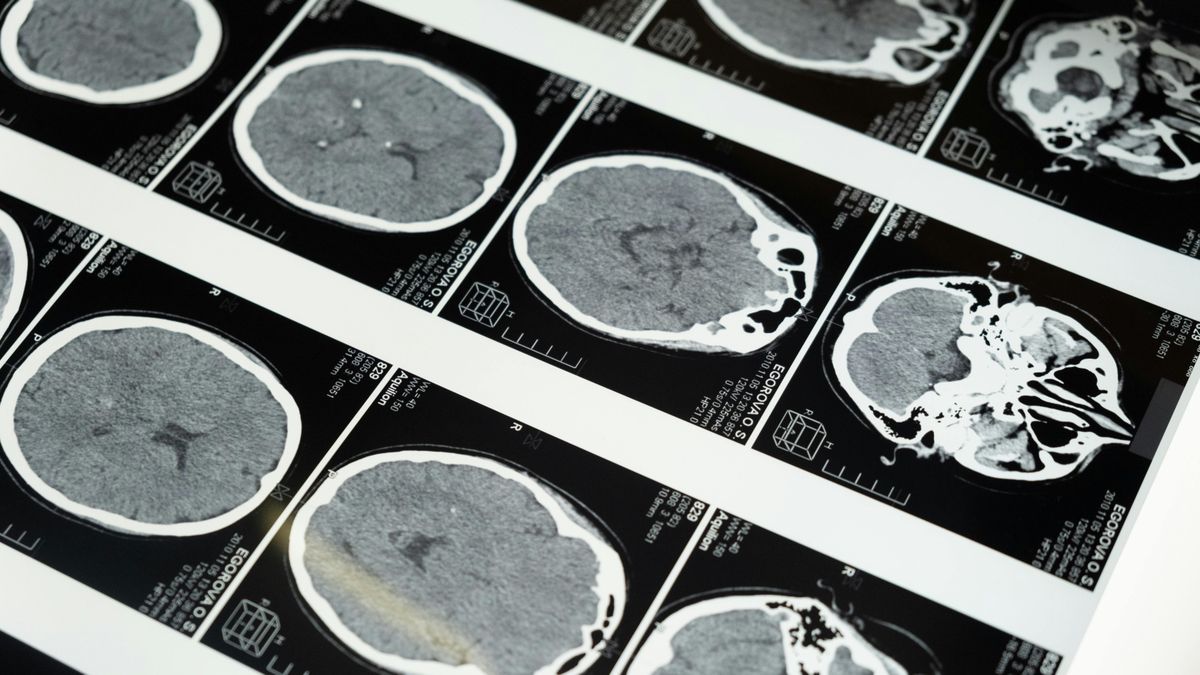

Engedélyezték a vérvizsgálatot, amely kimutatja az Alzheimer-kórt

A gerincvelőifolyadék-elemzés helyett ezután egy egyszerű vérvizsgálat mutathatja meg az orvosoknak, hogy egy adott beteg Alzheimer-kórban szenved-e. Az újfajta megoldást az Egyesült Államokban alkalmazhatják először.

Áttörés: egyszerű vérvizsgálat mutathatja ki a gyógyíthatatlan betegséget

Az amerikai Élelmiszer- és Gyógyszerügyi Hivatal (FDA) engedélyezte a Fujirebio Diagnostics vérvizsgálatát az Alzheimer-kór diagnosztizálására, amely az első ilyen jellegű teszt a betegség kimutatására.